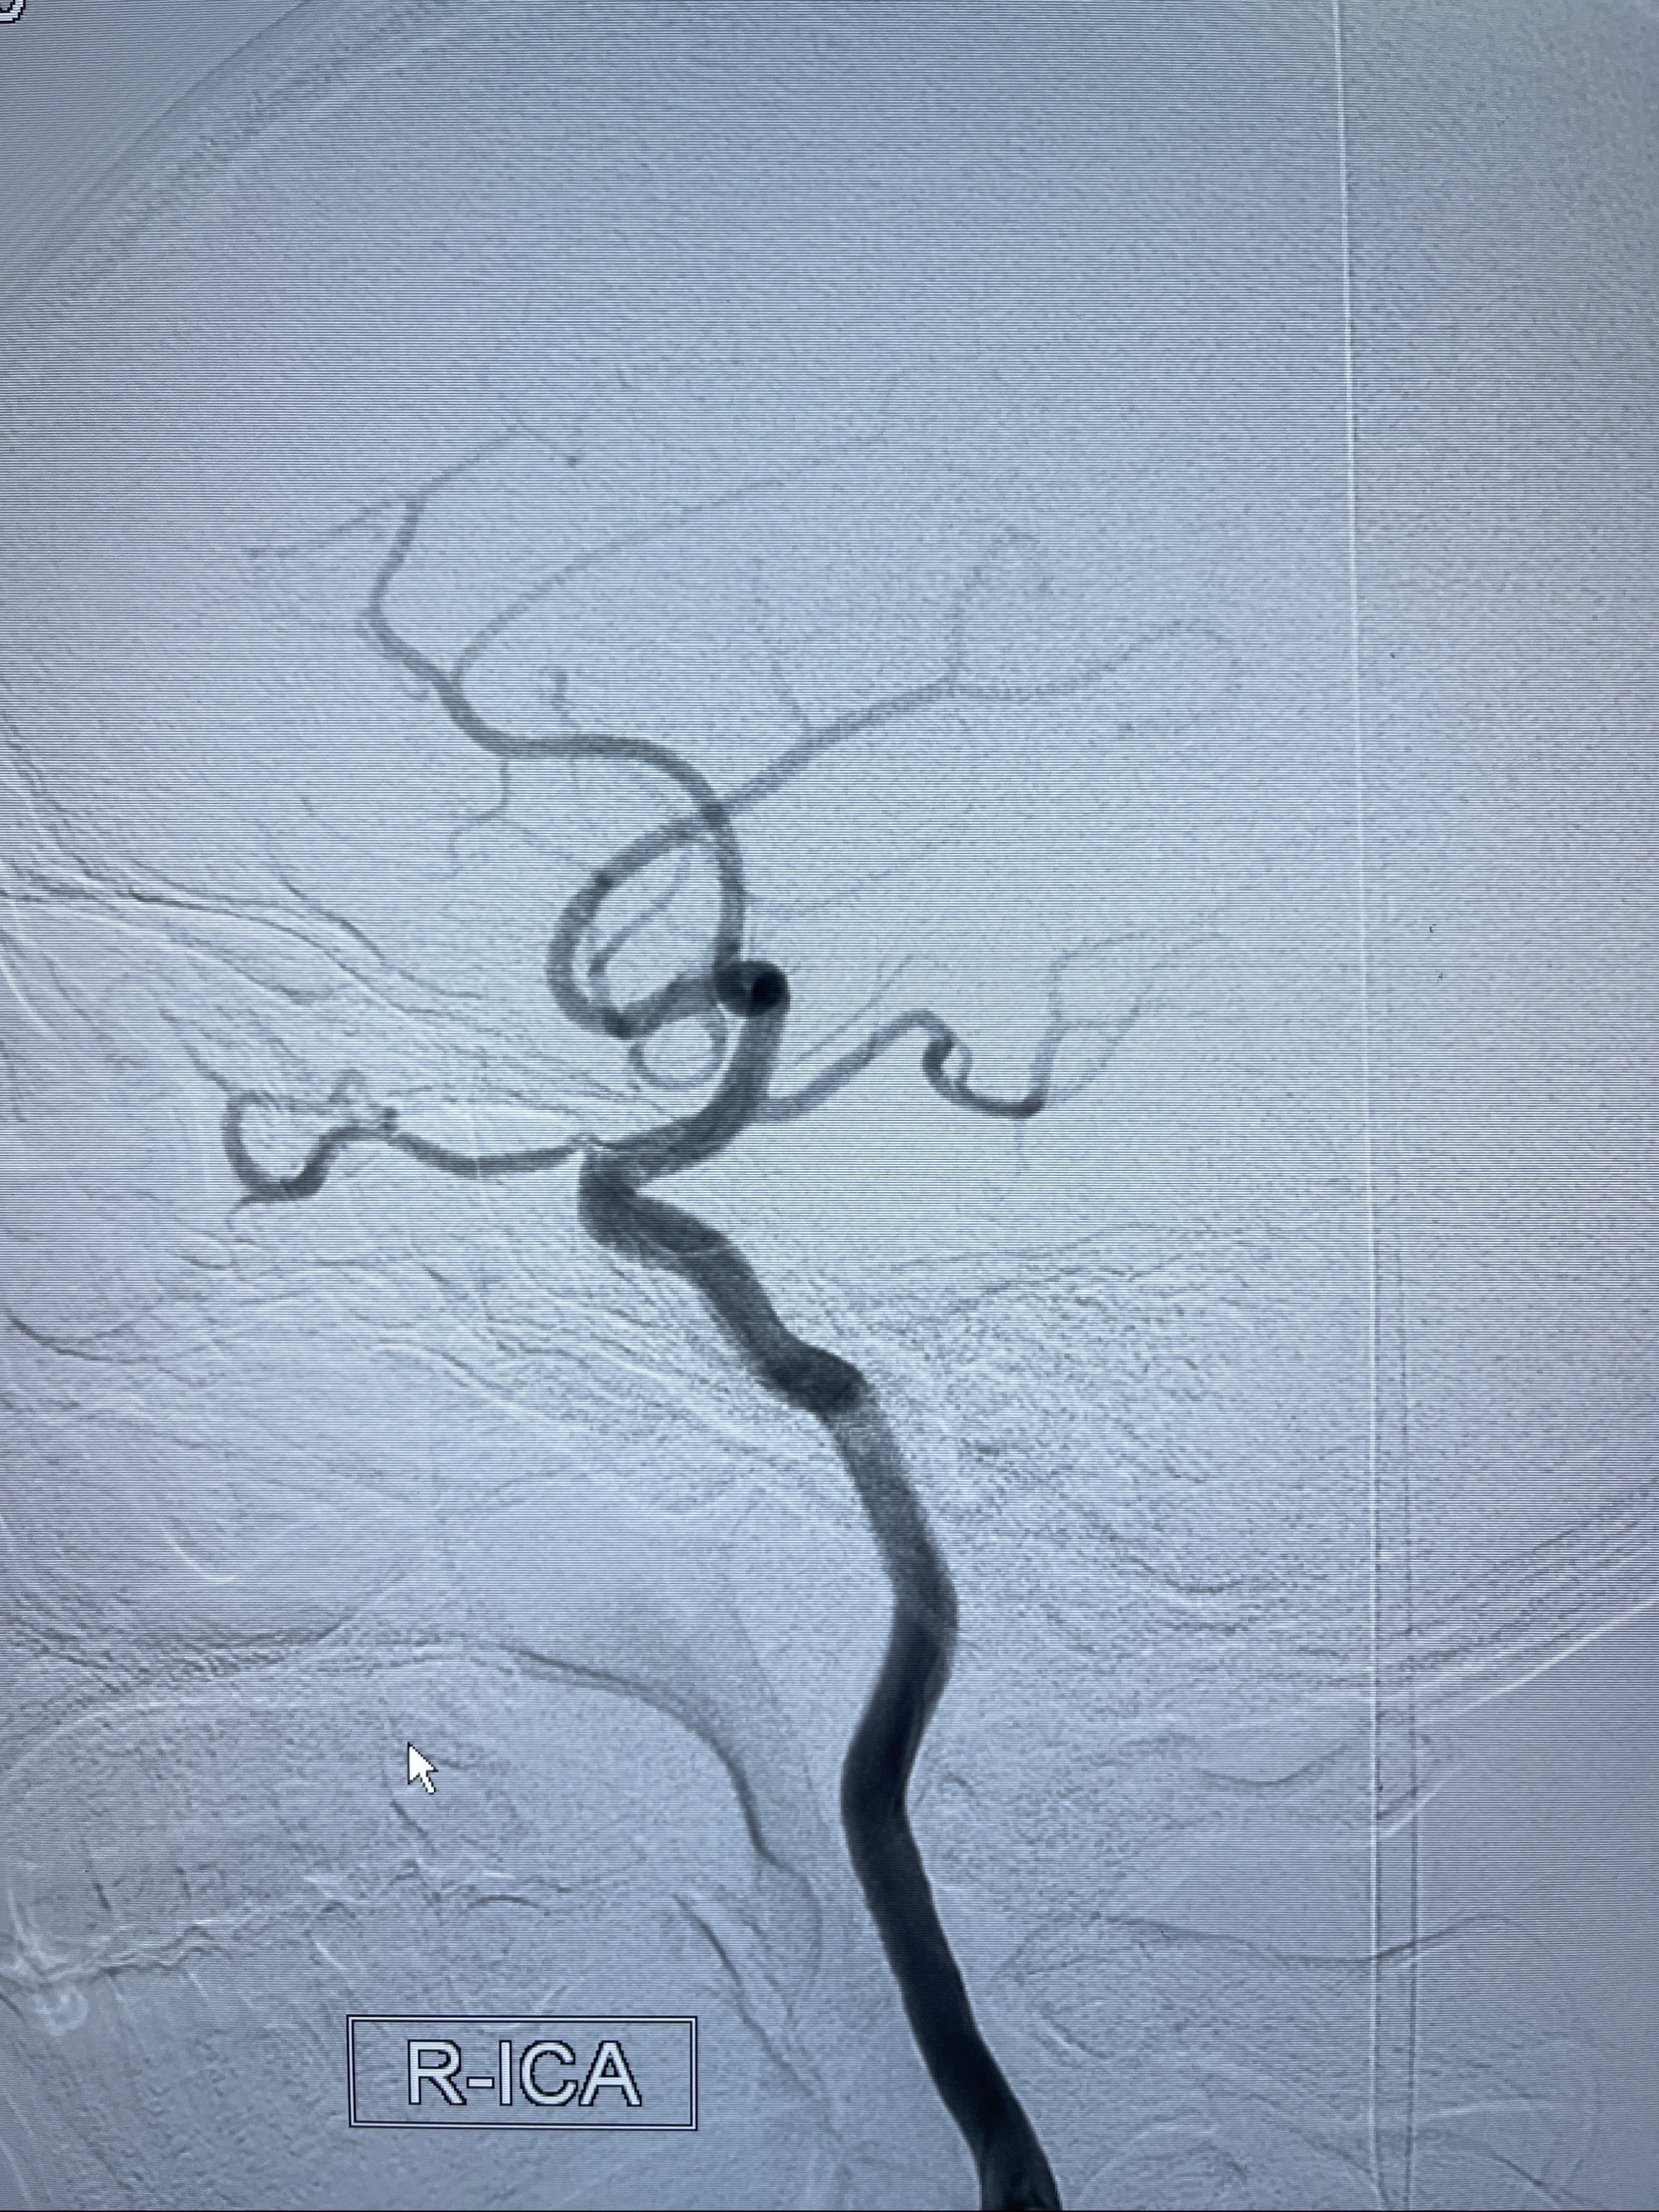

2023年8月21日]景德镇市第一人民医院脑血管造影检查,提示:主动脉弓、双侧颈总动脉、锁骨下动脉造影未见异常,左侧大脑前动脉静脉瘘。

2023-09-13全脑血管造影:前颅底硬脑膜动静脉瘘,供血动脉为双侧胼周动脉、眼动脉脑膜支,静脉向上矢状窦方向引流